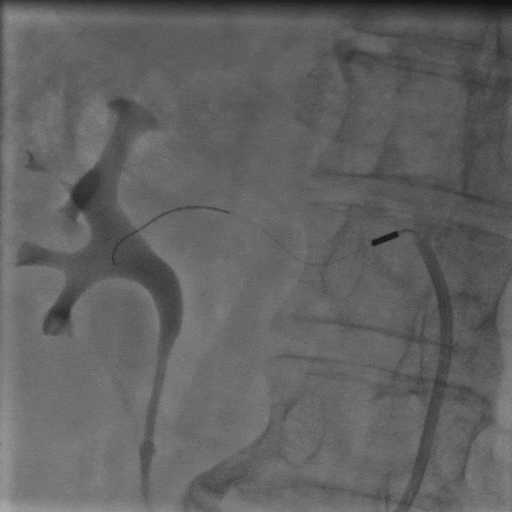

手術(shù)中,團(tuán)隊(duì)通過(guò)穿刺右側(cè)股動(dòng)脈,置入動(dòng)脈鞘和導(dǎo)管,對(duì)左右腎動(dòng)脈進(jìn)行造影評(píng)估后,使用Hawk Sonic超聲消融導(dǎo)管對(duì)腎動(dòng)脈分支及主干進(jìn)行消融治療。

術(shù)后患者血壓顯著下降,復(fù)測(cè)血壓149/72mmHg;手術(shù)次日血壓降至122/66mmHg,且術(shù)后2個(gè)月未發(fā)生任何不良事件,復(fù)查腎動(dòng)脈CTA未見(jiàn)狹窄等異常。

▲右側(cè)腎動(dòng)脈主干超聲消融